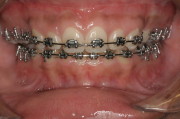

Case from Start to Finish

Finished Patient with a Perfect Bite and Excellent Facial Proportions